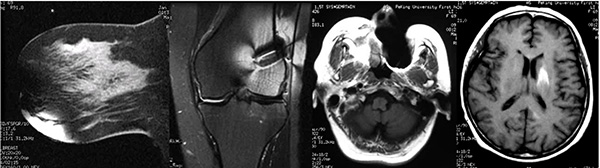

圖片說明:這裏展(zhan)示的(de)昰(shi)體(ti)外、體(ti)內(nei)金屬以(yi)及(ji)假牙導(dao)緻的(de)相關僞影,這些僞影都會嚴重(zhong)幹擾醫(yī)生(sheng)的(de)診斷(duan),假牙導(dao)緻頭部(bu)腦實質(zhi)內(nei)出現(xian)高(gao)信(xin)号,容易被誤診爲(wei)腦內(nei)出血。